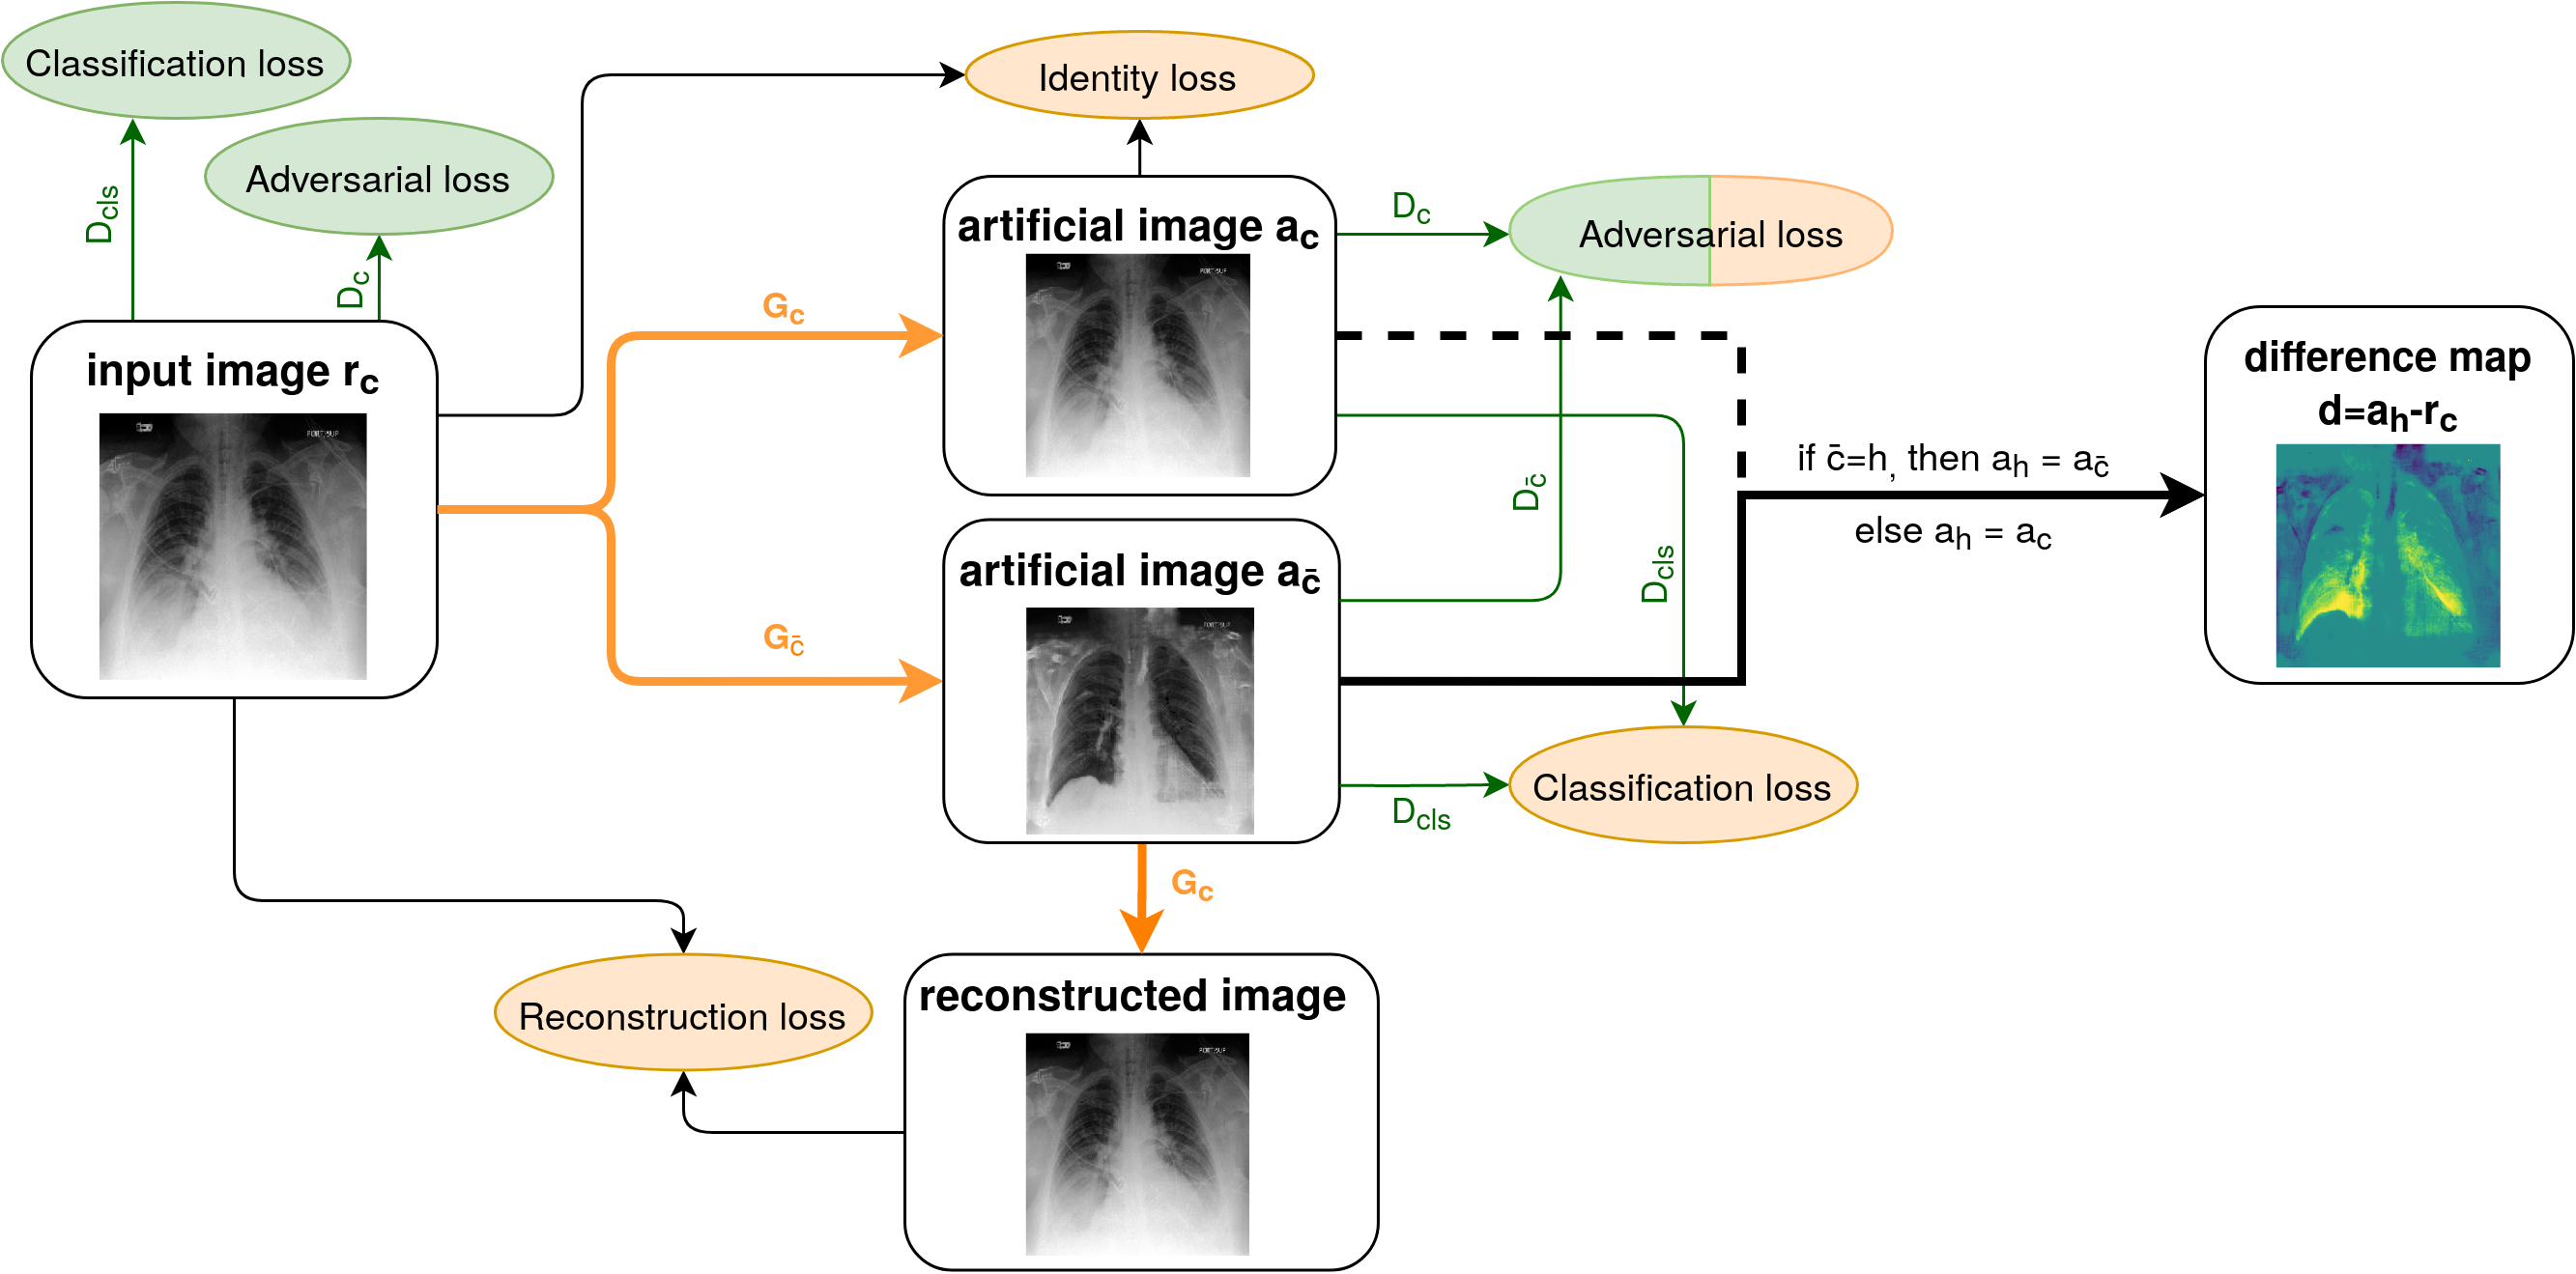

Thus we perform image-to-image translation between the unpaired sets and . A diagram showing the workflow of our method is given in Figure 1. Given any image , the generator both generates an artificial image of the same class and an artificial image of class . To ensure that and only differ in the pathological region, we add the identity loss and the reconstruction loss for cycle consistency.

The generator consists of two branches, its architecture is shown in Figure 2. We refer to the generator for generating images of class and generator for generating images of class .

The skip connections of the generator ensure that the artificial image maintains the detailed structures of the input image. This is a way to alter only the necessary features, thus making the difference map more accurate. The skip connection in the uppermost layer turned out to be too restrictive to perform the translation to another class. By omitting this skip connection, we enable the generator to perform structural changes.

The discriminator network has the task to both classify images into healthy and diseased subjects and to distinguish between real and artificial images. Therefore, it consists of three subnets that share parameters, as shown in Figure 3. distinguishes between real and artificial images of class , does the same for class and is the network for classification, following the structure of a VGG net [22]. The branching of the generator and discriminator gives a higher range of flexibility compared to StarGAN, which turned out to be beneficial for image-to-image translation.

With the notation from above, can be or interchangeably, and denotes the discriminator for the contrary class. The same applies for the generator .